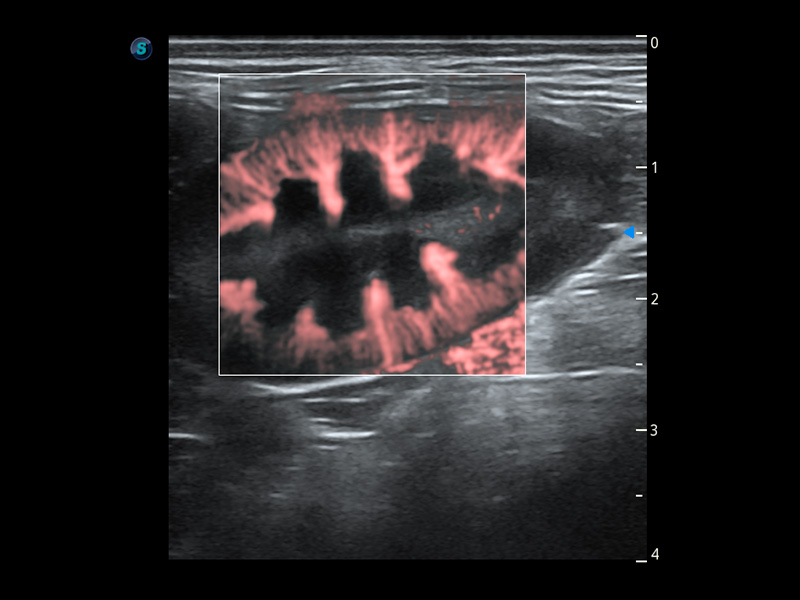

PDI 能量多普勒血流

提供高灵敏度和空间分辦率的血流图像,获得更加真实和丰富的诊断信息。

SR Flow 高分辨率血流成像

能够清晰显示细小、低速血流图像,获取传统彩色多普勒技术难以得到的细节和信息。

Micro F 显微血流成像

通过创新的Matrix E自适应滤波器和超长时间域算法,极大提升超低速微细血流的检出能力,同时更精准地滤除软组织和噪声信号,为兽用医生提供以往无法通过常规血流获得的疾病诊断信息。

Bright Flow 立体血流成像

在传统二维血流成像的基础上,呈现血流的立体感,具有动感的生命力之美。精确区分不同血管的空间关系,提高了血流的视觉敏感性。